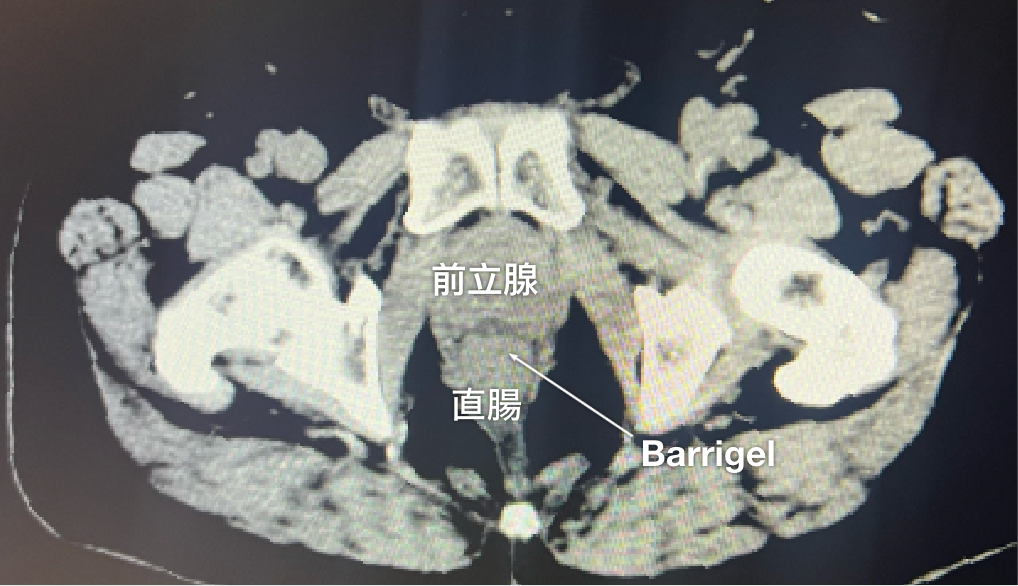

CT画像

CT画像提供:Suraj Singh, MD

Radiation Oncologist, Colorado, United States